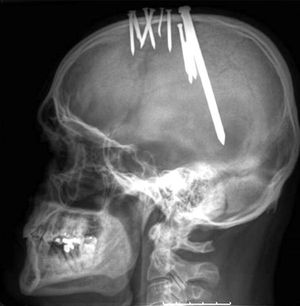

A horrible case of a 44 year psychiatric patient. Read the story!

A 44 year old man was referred to the accident and emergency department by the psychiatric services, having claimed to have hammered several nails through